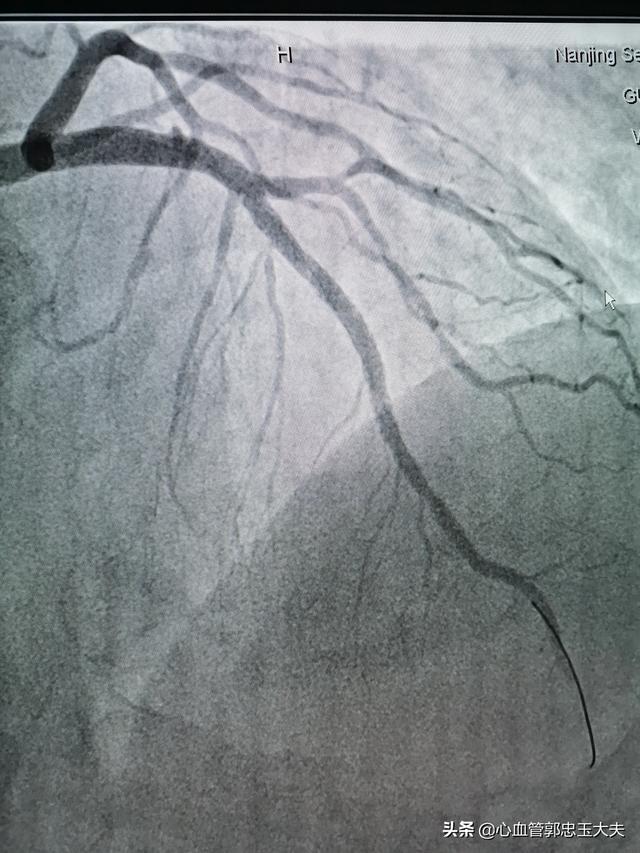

4.冠動脈造影冠動脈造影は現在でも冠動脈疾患の診断のゴールドスタンダードであるが、侵襲的で入院が必要である。

2.冠動脈造影

現在、心血管スクリーニングのゴールドスタンダードとなっているこの方法は、直感的で、介入策をタイムリーに知ることができるが、高価であり、危険でもある。

冠動脈造影

冠動脈造影検査は、冠動脈血管の走行と開存性を視覚的に観察・評価し、冠動脈病変の有無と病変の程度を評価し、左心機能を評価することができる冠動脈疾患の診断のゴールドスタンダードであり、これに基づいて冠動脈病変の程度に応じたインターベンション治療を実施し、冠動脈バイパス術やインターベンション後の治療効果を評価することができる。侵襲的診断法である冠動脈造影検査には、ヨードや造影剤に対するアレルギー、重症心肺機能不全、肝腎機能不全、不整脈、電解質異常などの禁忌があり、事故を避けるために実施できない。